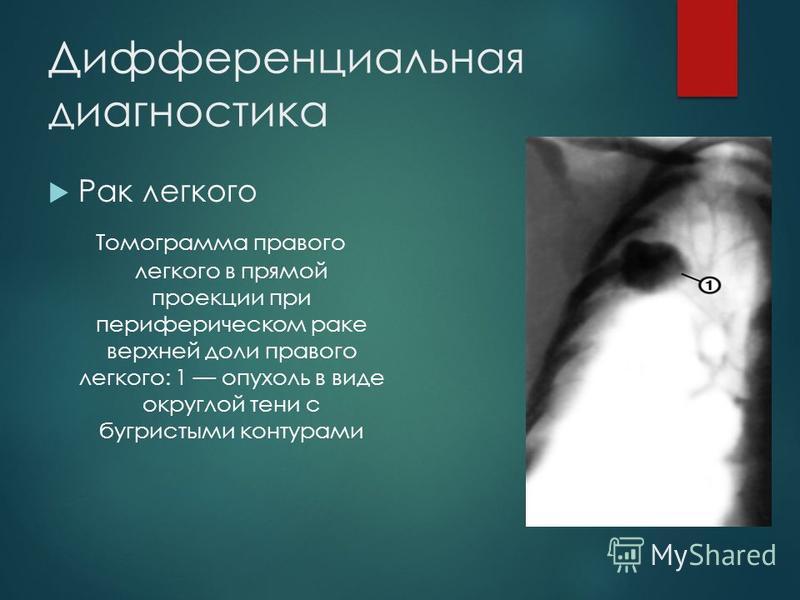

Дифференциальная диагностика заболеваний плевры